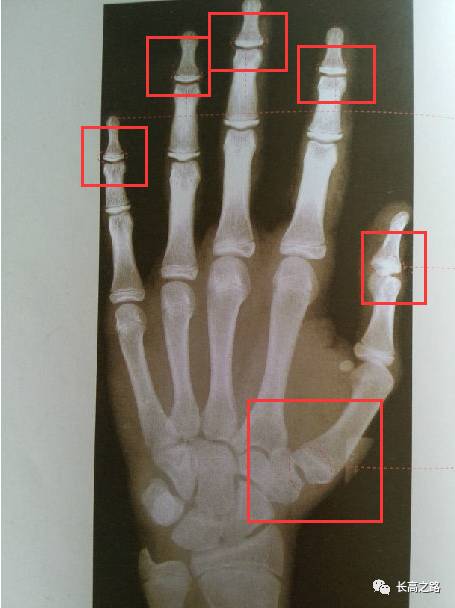

骨龄片怎么看

骨龄片怎么看,男孩骨龄图谱

教你简单识别孩子的骨龄片

收藏丨骨龄图谱方便随时对照

手的骨龄片对照表

儿童骨龄片对照表

如何看懂骨龄片

骨龄片对照表 女孩

女孩骨龄图谱

男孩各年龄段骨龄图

标准骨龄图谱

骨龄片

骨龄片对照表

骨龄片对照图

骨龄图片

骨龄图片对照表

骨龄图谱